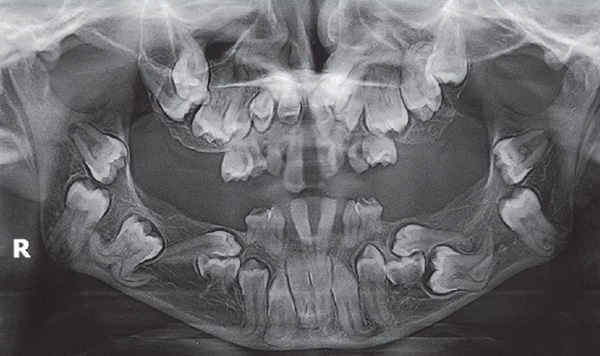

Para esclarecer as razões, o médico pode enviar a criança para um raio-x (o estudo é realizado estritamente de acordo com as indicações, para não prejudicar o corpo da criança com radiação excessiva). Os ortodontistas, por via de regra, enviam crianças para radiografias pela primeira vez aos 4-5 anos de idade para ver como a dentição é formada e que ações podem ser tomadas agora.

Antes de tudo, o médico está interessado em saber se todos os rudimentos do leite e dos dentes permanentes estão presentes, se eles estão localizados em seus locais anatômicos, que obstáculos no caminho do dente o impedem de deixar o osso. Junto com isso, chama-se a atenção para a estrutura do seio maxilar, canal mandibular e outras estruturas importantes da região maxilofacial.